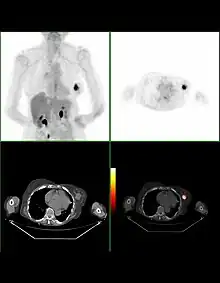

Bilan d'extension

La recherche de métastases est fondamentale dans la stratégie du traitement du cancer du sein. Mais, malgré les nombreuses études réalisées ou la connaissance approfondie de certaines explorations, il n'existe actuellement aucune stratégie validée de recherche systématique de métastase dans le cancer du sein.

La plupart des recommandations proposent actuellement un bilan d'extension comportant un examen clinique soigneux à la recherche de métastases ganglionnaires, une radiographie thoracique, une échographie hépatique et une scintigraphie osseuse. Pour les tumeurs de très petite taille, ce bilan peut être facultatif. En revanche, pour les tumeurs évoluées (tumeurs inflammatoires, multi-focales, envahissement ganglionnaire important), le risque métastatique initial est élevé et peut justifier un bilan plus poussé comportant une Tomodensitométrie (TDM) corps entier et une IRM mammaire.